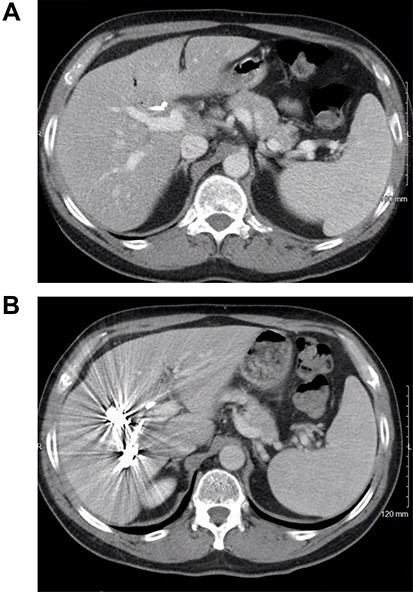

A 59-year-old male presented with abdominal pain for several months. Computed tomography (CT) showed a 9.3-cm gallbladder mass with direct extension into the right and left hepatic lobes (Fig. 1A), porta hepatis and mesenteric fat. Biopsy established a poorly differentiated adenocarcinoma of gallbladder origin. Biliary obstruction at the level of the common and cystic duct junction was managed with internal biliary stenting. The process presented as cT3N1M0, locally advanced, and not completely resectable gallbladder adenocarcinoma; serum CA 19–9 level was 2666 U/ml (normal up to 35 U/ml).

(A) CT scan of the abdomen showing the thickened gallbladder as well as a mass involving hilar hepatic parenchyma; (B) treatment response after immunotherapy.

The patient received systemic chemotherapy with gemcitabine and cisplatin. After more than 2 months, he developed grade 3 neuropathy and experienced several episodes of cholangitis with liver abscess and bacteremia requiring multiple stent exchanges, and systemic therapy was discontinued. He then received trial-based immune check point inhibition with ipilimumab and nivolumab. There was good radiological (Fig. 1B) and tumor marker response (CA 19–9 7.05 U/ml). Immunotherapy had to be stopped after 10 months due to grade 3 autoimmune hepatitis. He was treated with oral steroids and immunosuppression with mycophenolate mofetil, resulting in the normalization of liver function tests. A R0 resection was now deemed a possibility, with a goal of best tumor control and long-term biliary decompression. He underwent right portal vein embolization after which his left lobe future liver remnant grew from 28 to 45% at a kinetic growth rate of 5.6% per week (Fig. 2). He underwent extended right hepatectomy with radical cholecystectomy, portal and hepatic artery lymph node dissection, and Roux-Y hepaticojejunostomy biliary reconstruction (Fig. 3). Pathology examination revealed a 6.5-cm gallbladder and hepatic tissue mass with xanthogranulomatous inflammation and nodular fibrosis, without residual viable tumor, margins free of carcinoma and 0/17 lymph nodes involved, consistent with an ypT0N0M0 gallbladder cancer, R0 resection. After an initial postoperative surgical site infection, he has now fully recovered and is disease-free at 10-month follow-up.